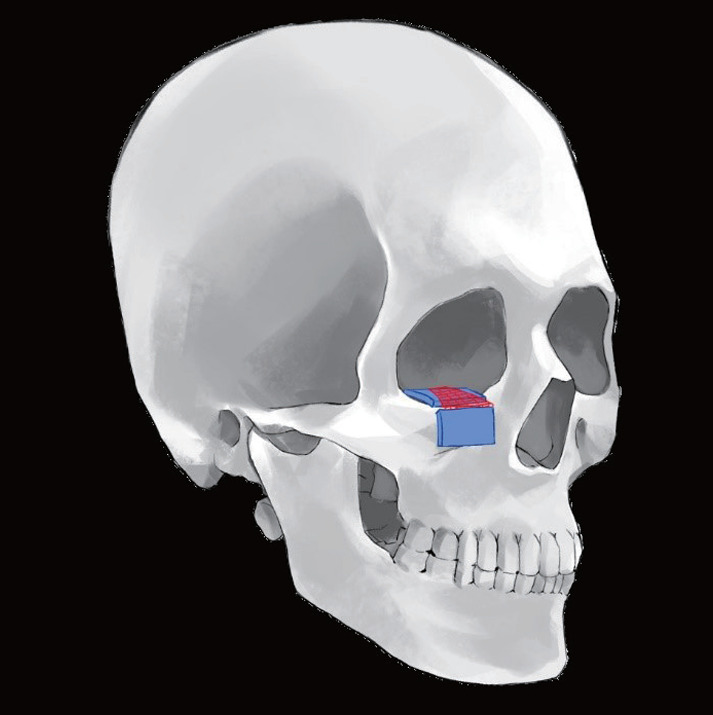

This paper presents a novel approach to the correction of zygomatic malposition and secondary reconstruction orbital floor fractures, highlighting the use of hydrated acellular dermal matrix (ADM), specifically CGDerm One-Step, in a case where traditional solid implants failed to maintain structural integrity and volume. A 27-year-old woman with persistent facial deformities following a traumatic incident underwent a transformative procedure that utilized ADM for volume correction and structural support, addressing significant challenges such as enophthalmos and facial contour depression. This approach was necessitated by the descent of the entire orbital floor and a previously placed implant (Medpor), leading to unsatisfactory volume correction. By integrating ADM with titanium-reinforced fan plates (Synpor), the surgery successfully restored the patient's facial symmetry and addressed her functional concerns, including diplopia and limited eye movement. Postoperative evaluations demonstrated the long-term effectiveness of this method, with significant improvements in facial contour and eye symmetry. Our findings suggest that ADM, particularly in its hydrated form, offers a reliable alternative to traditional bone grafts and implants for correcting complex craniofacial deformities, providing both aesthetic and functional benefits. This case underscores the importance of adaptable, tissue-mimicking materials in facial reconstructive surgery, offering insights into their potential for broader application in post-traumatic facial corrections.